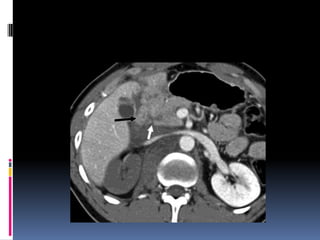

 Segundo órganomas afectado  Lesiones similares a las hepáticas  Sospecha de lesión:  Contornos borrosos  Líquido espacio pararrenal anterior y lateroconal izquierdos  Coágulo centinela

 Pitfalls:  Hendiduras (cleft) congénitos  Artificios de costillas, interfases aire-líquido (estómago, intestino), sondas o catéteres metálicos  Heterogeneidad fase arterial